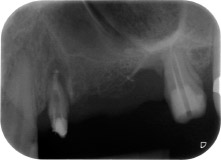

Después de la medicación tópica con un 25 % de gel de metronidazol (Elyzol) en las bolsas de la pieza 24, se inició un tratamiento causal de terapia periodontal con desinfección de toda la boca. El tratamiento ortógrado del canal radicular se revisó mediante una obturación con gutapercha termoplástica, un poste de fibra de vidrio y una acumulación de núcleo de composite (figura 2). El puente se recementó fuera de la oclusión para permitir la cicatrización sin problemas de los lugares de la GTR y la GBR.

Un mes después, en el día de la intervención, el dolor y la inflamación se habían reducido al mínimo en la pieza 24, pero seguía habiendo una movilidad de clase II de Miller. Después de la apertura de los colgajos y de la limpieza del tejido infectado periapical y perirradicular, la extensión del defecto óseo quedó evidente (figuras 2 y 3).